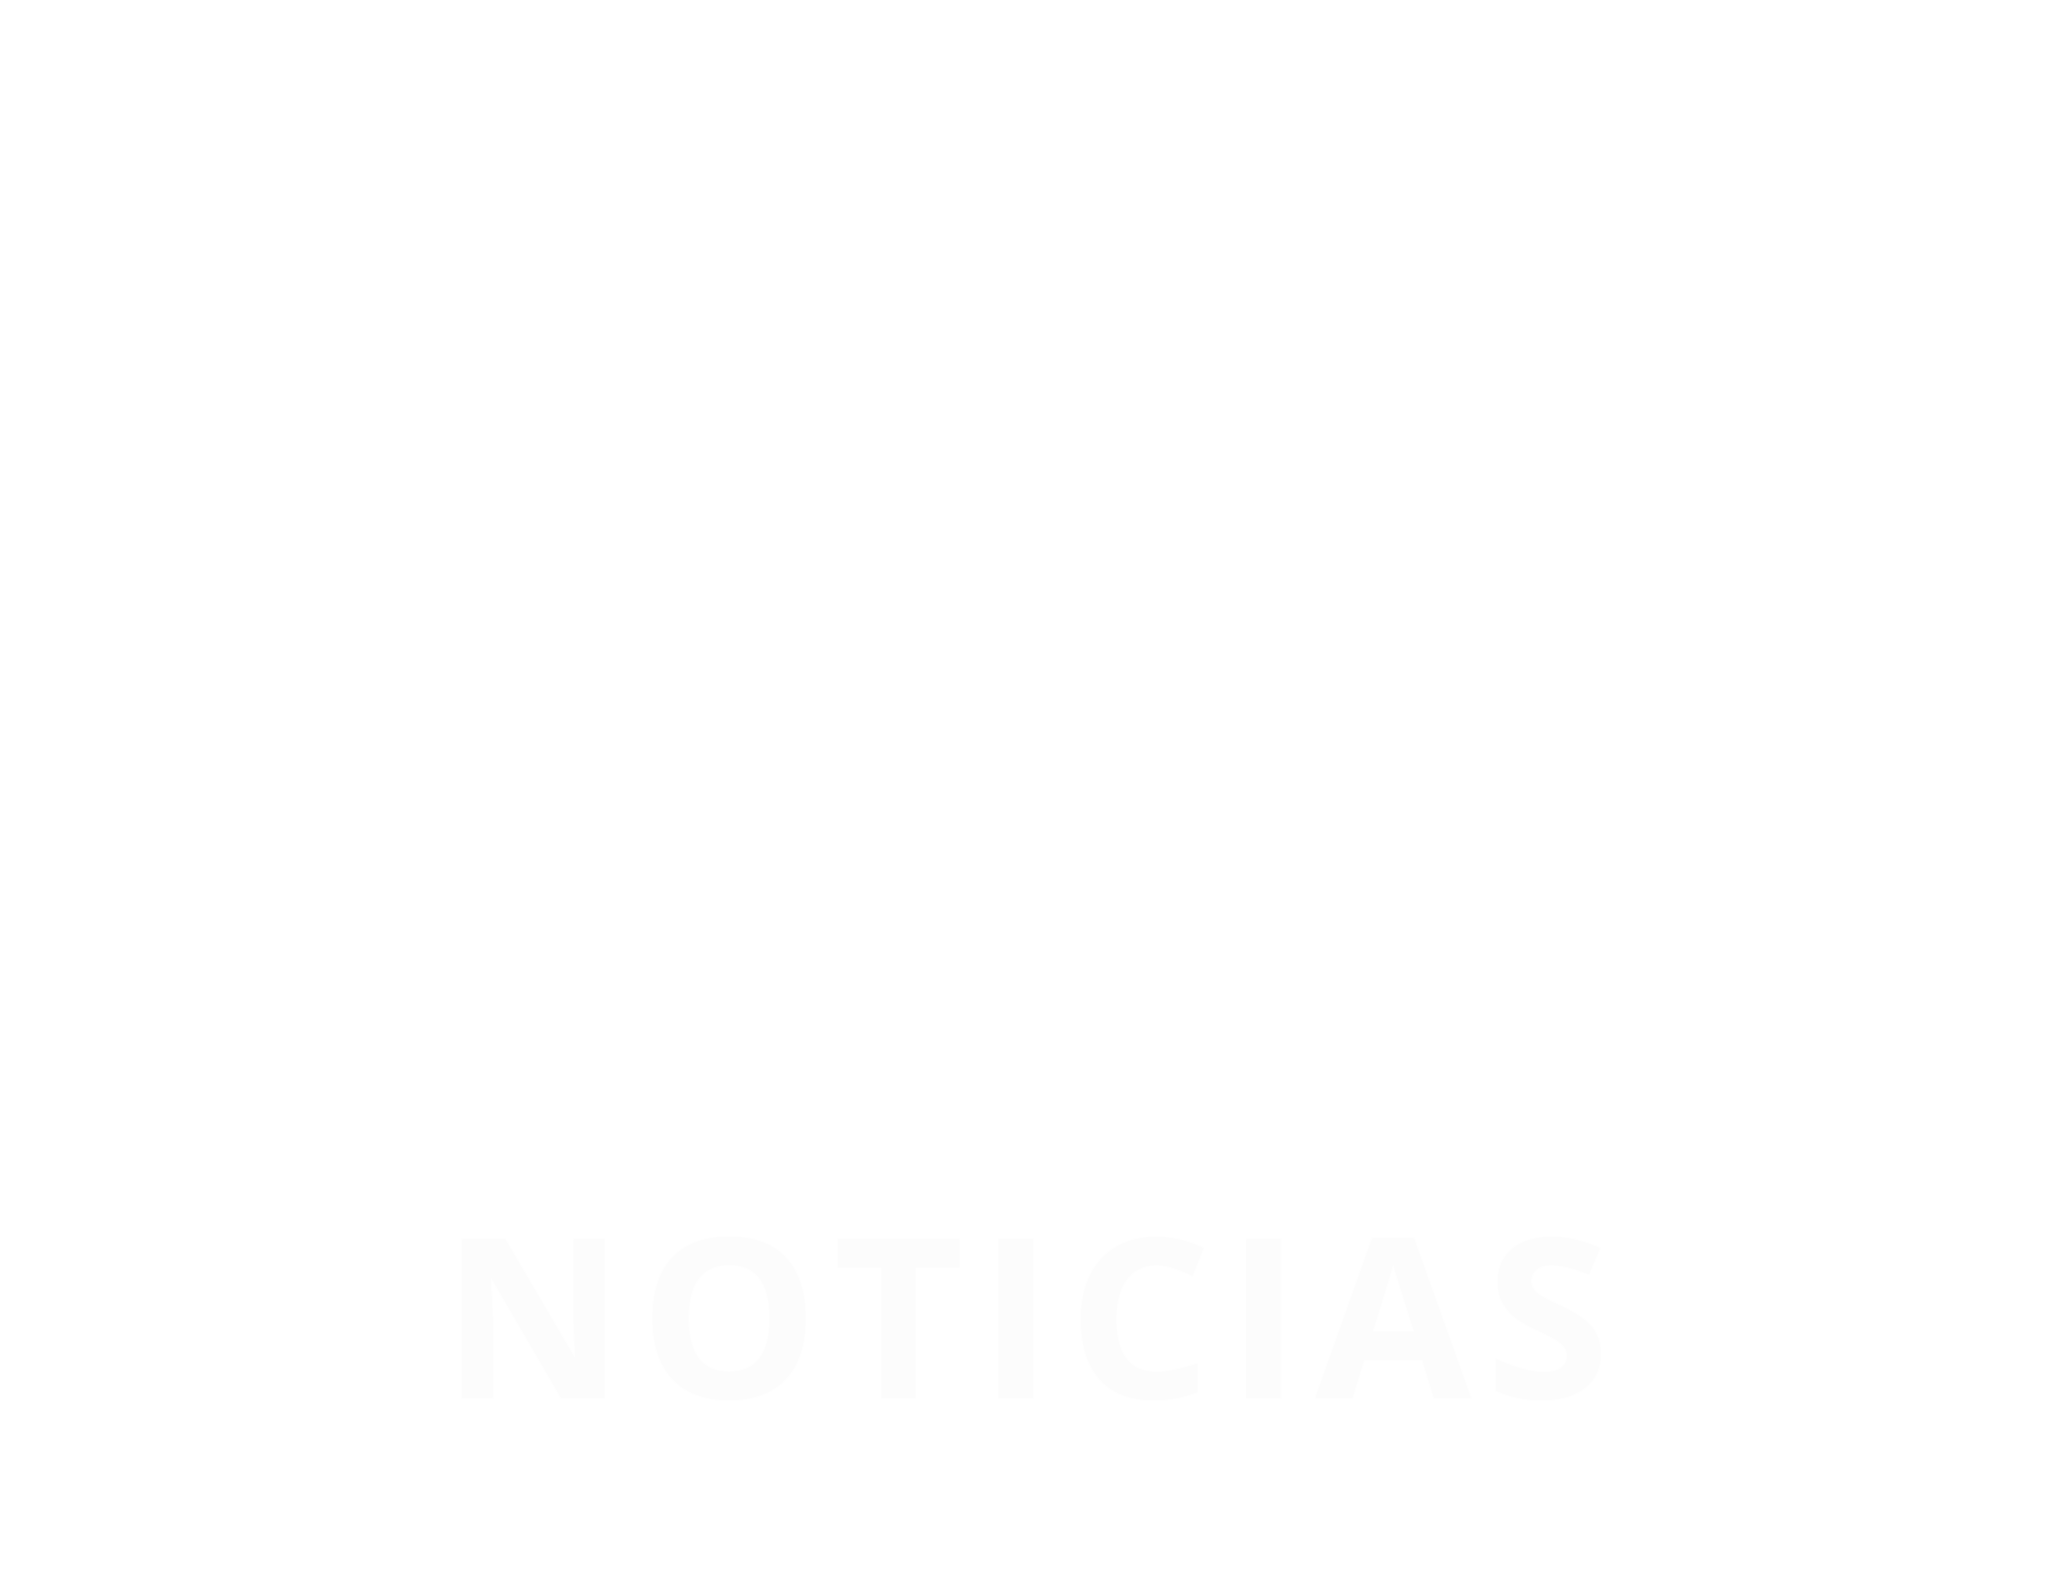

En diciembre de 2018, el Secretario de Estado de Salud y Asistencia Social permitió a las mujeres autoadministrarse la segunda parte de un aborto con medicamentos en casa, y esta medida se amplió a ambas partes del proceso en marzo de 2020 como respuesta a los confinamientos por la pandemia de Covid-19.

El Real Colegio de Obstetras y Ginecólogos (RCOG) advierte que 1% de todos los casos de aborto con medicamentos fracasan, mientras que hasta el 6% pueden ser incompletos, lo que requiere atención médica adicional. Sin embargo, los proveedores de servicios de aborto y el Departamento de Salud y Asistencia Social han subestimado estas complicaciones, según el informe reciente.

LEE Debaten sobre deshumanización y lucro detrás de ‘derecho al aborto’ en el ITAM

El análisis de datos revela que el 2.8% de las mujeres que autogestionaron sus abortos con medicamentos en casa fueron admitidas posteriormente en hospitales para recibir tratamiento quirúrgico, lo que sugiere una tasa total de complicaciones del 6%. Estas cifras, consistentes con investigaciones independientes, plantean serias preocupaciones sobre la seguridad y el apoyo a las mujeres que optan por el aborto con medicamentos en el hogar.

El aumento de abortos registrados en el primer semestre de 2022, con un incremento del 17% en comparación con el mismo período de 2021, es un indicador adicional de la magnitud del problema. Organizaciones independientes han expresado su preocupación por el impacto emocional y físico en las mujeres, así como por la falta de apoyo adecuado en este proceso.